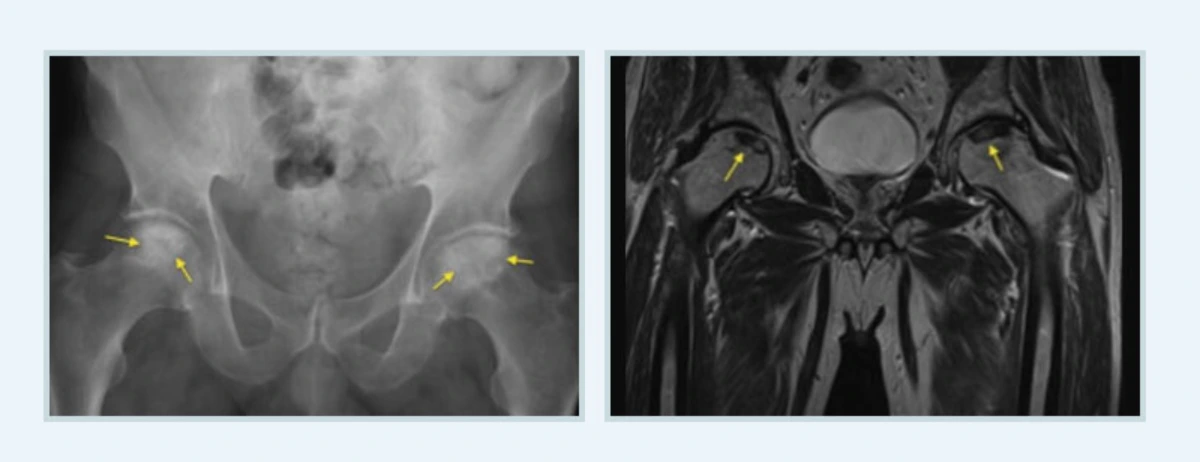

대다수 병이 그렇지만 대퇴골두무혈성괴사는 괴사가 발생함과 동시에 증상이 나타나지 않는 것이 문제입니다. 괴사가 시작되고 수개월이 지나서 골두에 골절이 생기면서 나타나지요.

이런 이유로 MRI로 정확한 대퇴골두의 상태를 확인하고 치료를 해야 하는데요. 괴사가 있으나 아직 미미한 상태라면 X-ray로는 상태를 정확히 확인할 수 없어 MRI를 해야 합니다.

캡처1.PNG

전영식 원장님“만약 치료를 하지 않고 자연히 나아지기를 기대하고 그냥 둔다면 20%가 1년 이내에 75%가 3년 이내에 대퇴골두의 붕괴가 나타납니다. 일단 썩은 뼈는 자연적으로 좋아지기는 어렵기 때문이지요. 따라서 병의 진행정도나 병변의 크기와 위치, 관련된 원인인자에 따라 적절한 치료가 이루어져야 합니다”라고 당부하시네요.